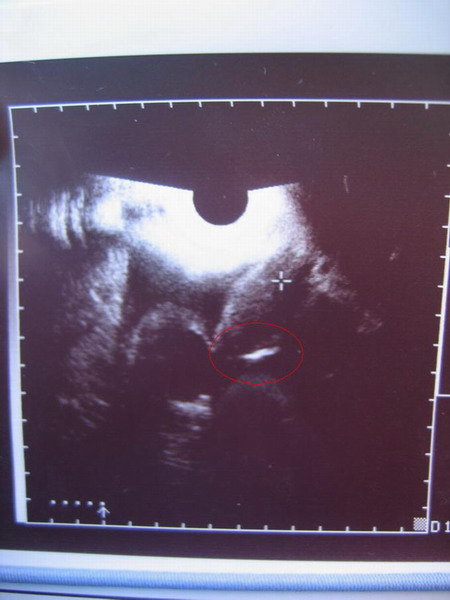

Na, hát ez is elérkezett… holnap reggel punkció. Para kezd lenni, de még nem vészes, jön Zozó is, úgyhogy majd nyugtatgathatom Őt

Amúgy pocim már nagyon feszít (főleg a bal oldalon), úgyhogy remélem lesz megkönnyebbülés is holnap.

Igen, tegnap este megvolt a tüszőrepi injekció, nem fájt, meg semmi. A torkom még mindig fáj, de nem érdekel. Ittam ma sok mézes teát, ettem egy mucoangint, ennyi. Csak elég